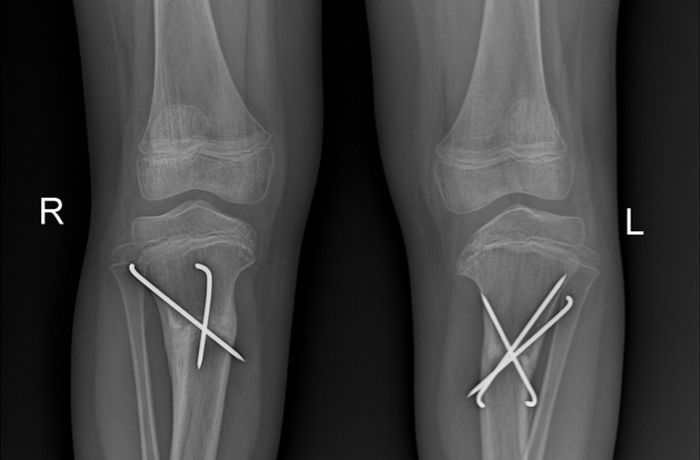

Parantezler ve bacaklar

Yürürken uzuv yerleşimine veya uzuv yerleşiminin kötü olmasına odaklanan bozukluk